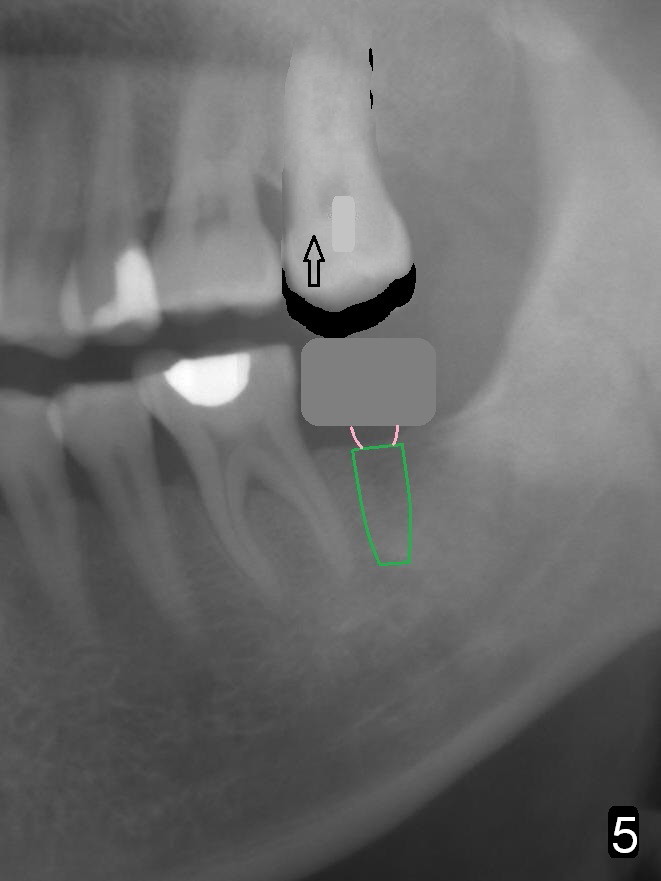

Next appointment, place 2 of mini-implants for #15 intrusion (Fig.1 arrow): one in MB (latch driver) and the other in DL (hand instrument).

In fact, the tooth 15 had basically no extrusion 6 years earlier (Fig.2) with even occlusal plane. When the tooth is intruded orthodontically, the occlusal plane may be not even (Fig.3). When the implant at #18 osteointegrates (Fig.4 green), fabricate a provisional (grey rectangle) with higher mesial occlusal surface. For certain period of time, the tooth #15 may change its axis so that the mesial portion of the tooth may be intruded more (Fig.5 arrow).

Four months post intrusion, the tooth #15 is distalized instead (Fig.9 arrow). To facilitate mesialization, the power chain is engaged into the mesiobuccal slot (Fig.10 <). It is 1 month after the change in position of the power chain. Has the tooth mesialized? Regional orthodontic devices are placed, but the patient is not cooperative, refusing any intrusion treatment. Prosthetic intrusion will be tried once the implant at #18 osteointegrates.